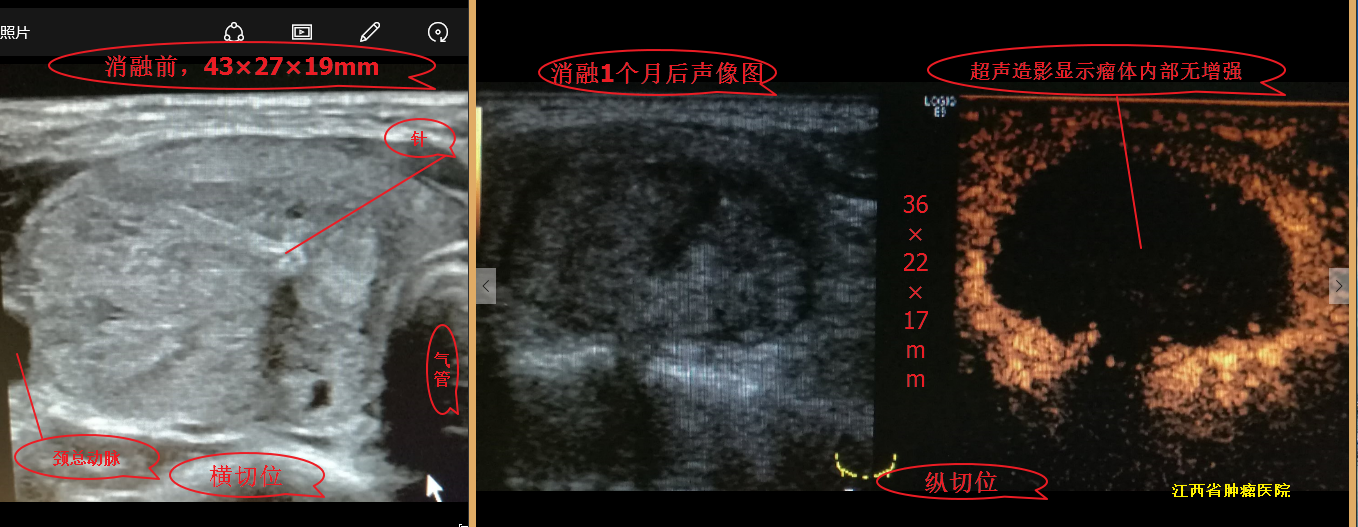

甲状腺结节微波消融术后,随访效果图!